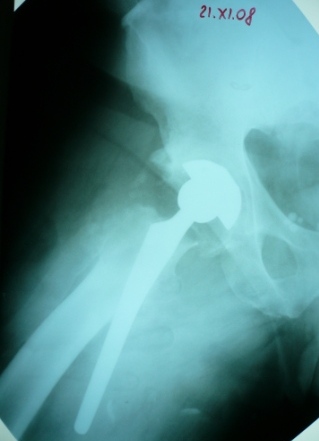

Больное выписан. Рекомендована ходьба без нагрузки 6 нед, рентгеноконтроль через 2 мес. Явка на консультацию На консультации через 7 недель-

Больной ходит с дозированной нагрузкой, умеренные боли по задней поверхности правого бедра.  Планируется ревизия. Удаление ножки. Установка такой же ножки Corail.

Приходилось ли кому встречаться с такой ситуацией?

Вопросы: вросла ли ножка? Какие могут возникнуть сложности с удалением ножки? Нужна ли будет дополнительная трепанация диафиза? И как? Правильный выбор ножка Corail для ревизии в такой ситуации?